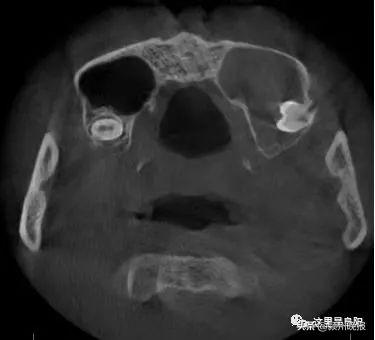

經(jīng)檢查

一顆智齒長到了他的鼻子里

小劉的智齒位于竇腔底部

與鼻子上頜竇僅一膜之隔

而這層膜比蛋殼還要薄